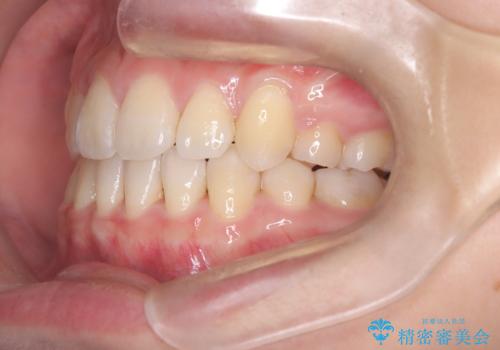

- 八重歯を主訴に来院されました。

左側犬歯が埋伏していましたが、第一小臼歯(4番目の歯)を抜歯したことでできたスペースに牽引し、右側の飛び出した八重歯を含め、歯全体を整列することができ患者様も満足していただきました。